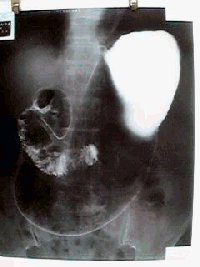

実際の胃の写真です |